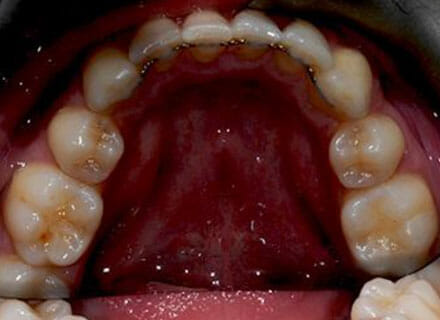

In this case, we needed to reduce the size of the central incisors as they were just too big. This combined with the crowding at the front had caused the lateral incisors to become trapped inside, pushing the big central incisor teeth forwards even more. After reducing the big teeth to a normal size we started with fixed clear bracket brace treatment and were able to complete this case in a little over a year.